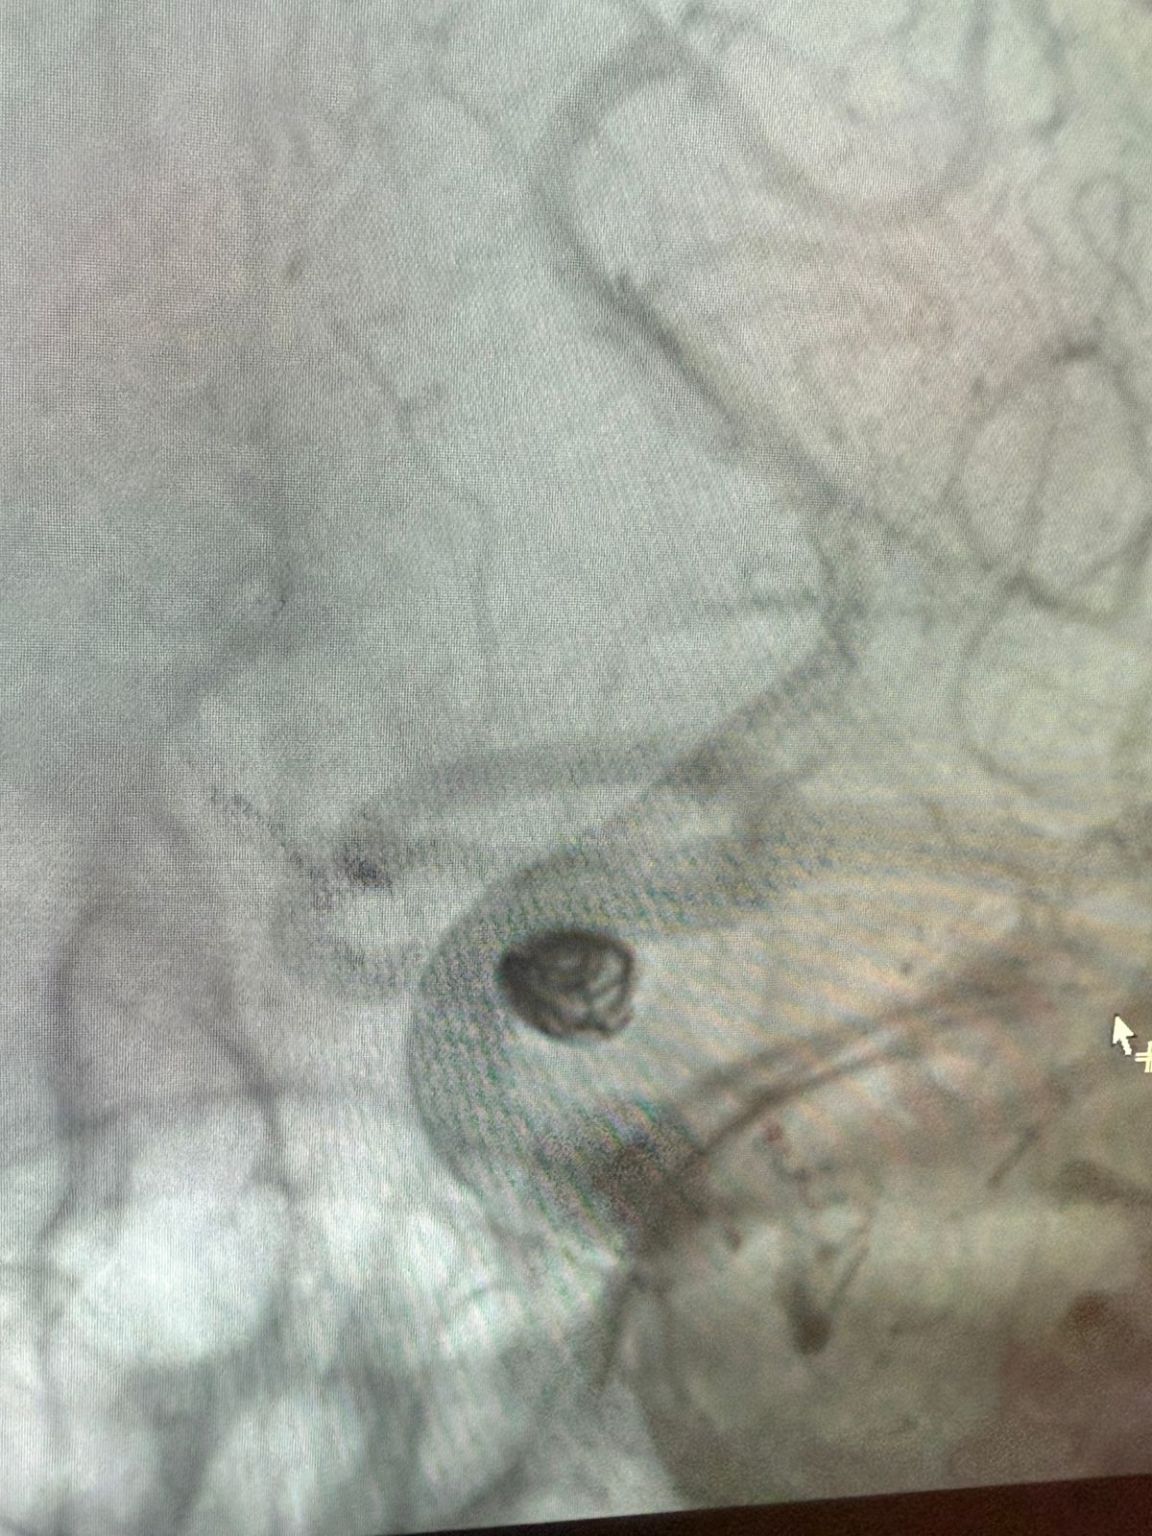

Die Behandlung nutzte die Nuva®Durchfluss-Diver ter (TJED-D 5.0-14), Perdenser®3D-Spule und Frepass®Mikro katheter (TJMC18 Plus) für ein posterior kommunizieren des Arterien aneurysma.